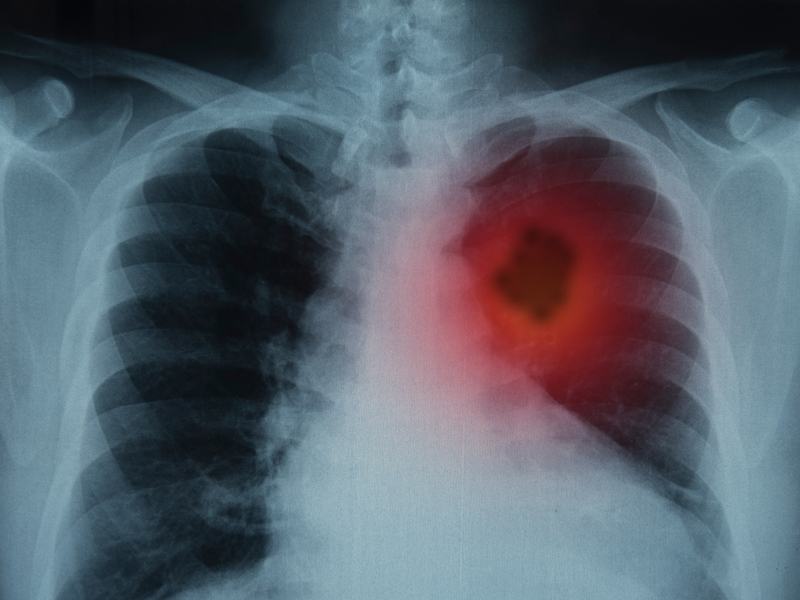

睡覺出現4種不適,可能是肺癌發出的信號

二、睡覺出現4種異常,或是肺癌信號

肺癌並不是無跡可尋,尤其是睡覺時,出現這幾種信號,就要警惕可能與癌症有關: